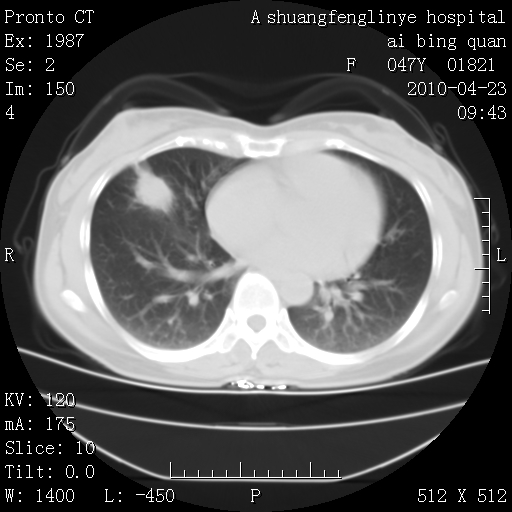

标题: CT25944:胸痛、气短、前几日高烧!肺Ca?请会诊! [打印本页]

标题: CT25944:胸痛、气短、前几日高烧!肺Ca?请会诊!

双肺多发结节,考虑转移瘤,肺癌肺转移不除外

双肺多发结节,部分密度较高,最大结节边缘光滑。临床有“胸痛、气短、前几日高烧”病史。首选考虑:右肺感染性病变!建议积极消炎后复查!